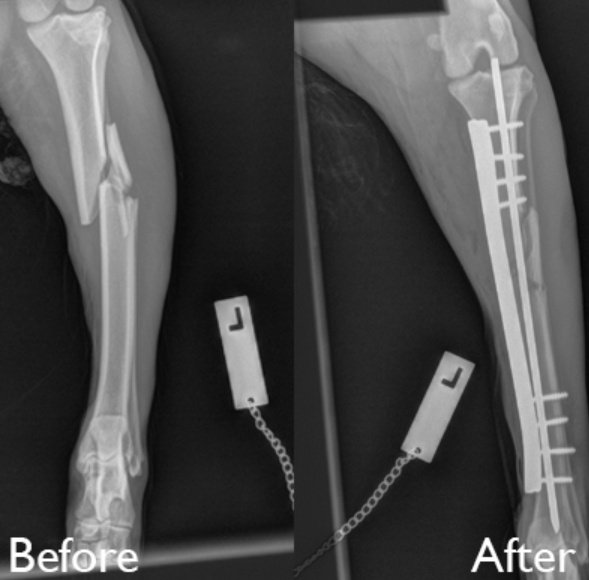

الكسور:

اكتر اشي معرض للكسر بالكلاب والبسس هم الارجل و الذيل. اهم اعراض الكسر انو الحيوان بضل رافع رجله وما بحطها عالارض ابدا ومبين الوجع. ضروري جدا تخلي الحيوان بمكان هادي وما تلعب بمكان الكسر، مهما كان الكلب اليف وبحبك راح يعضك لانو موجوع.

لانو لما تتوجع بتفضل تقعد بمكان في خصوصية شوي. وغير هيك *ضروري جدا* ما حد يحاول يجبر الكسر لحالو بالبيت. انت هيك ممكن تخلينا نخسر الطرف المكسور. بس اتركه لحاله. حاول خلي طبيب يشوفو بنفس اليوم بدون تاخير

بالنسبة للذيل بالعادة بطيب لحاله هو، بس مرات بتقدر تحس بالكسرات مع الوقت بصير زي مفاصل انو بتلاقي الذيل زي حرف L صار. بس اكيد اذا تعالج صح بوقتها برجع كل اشي طبيعي.